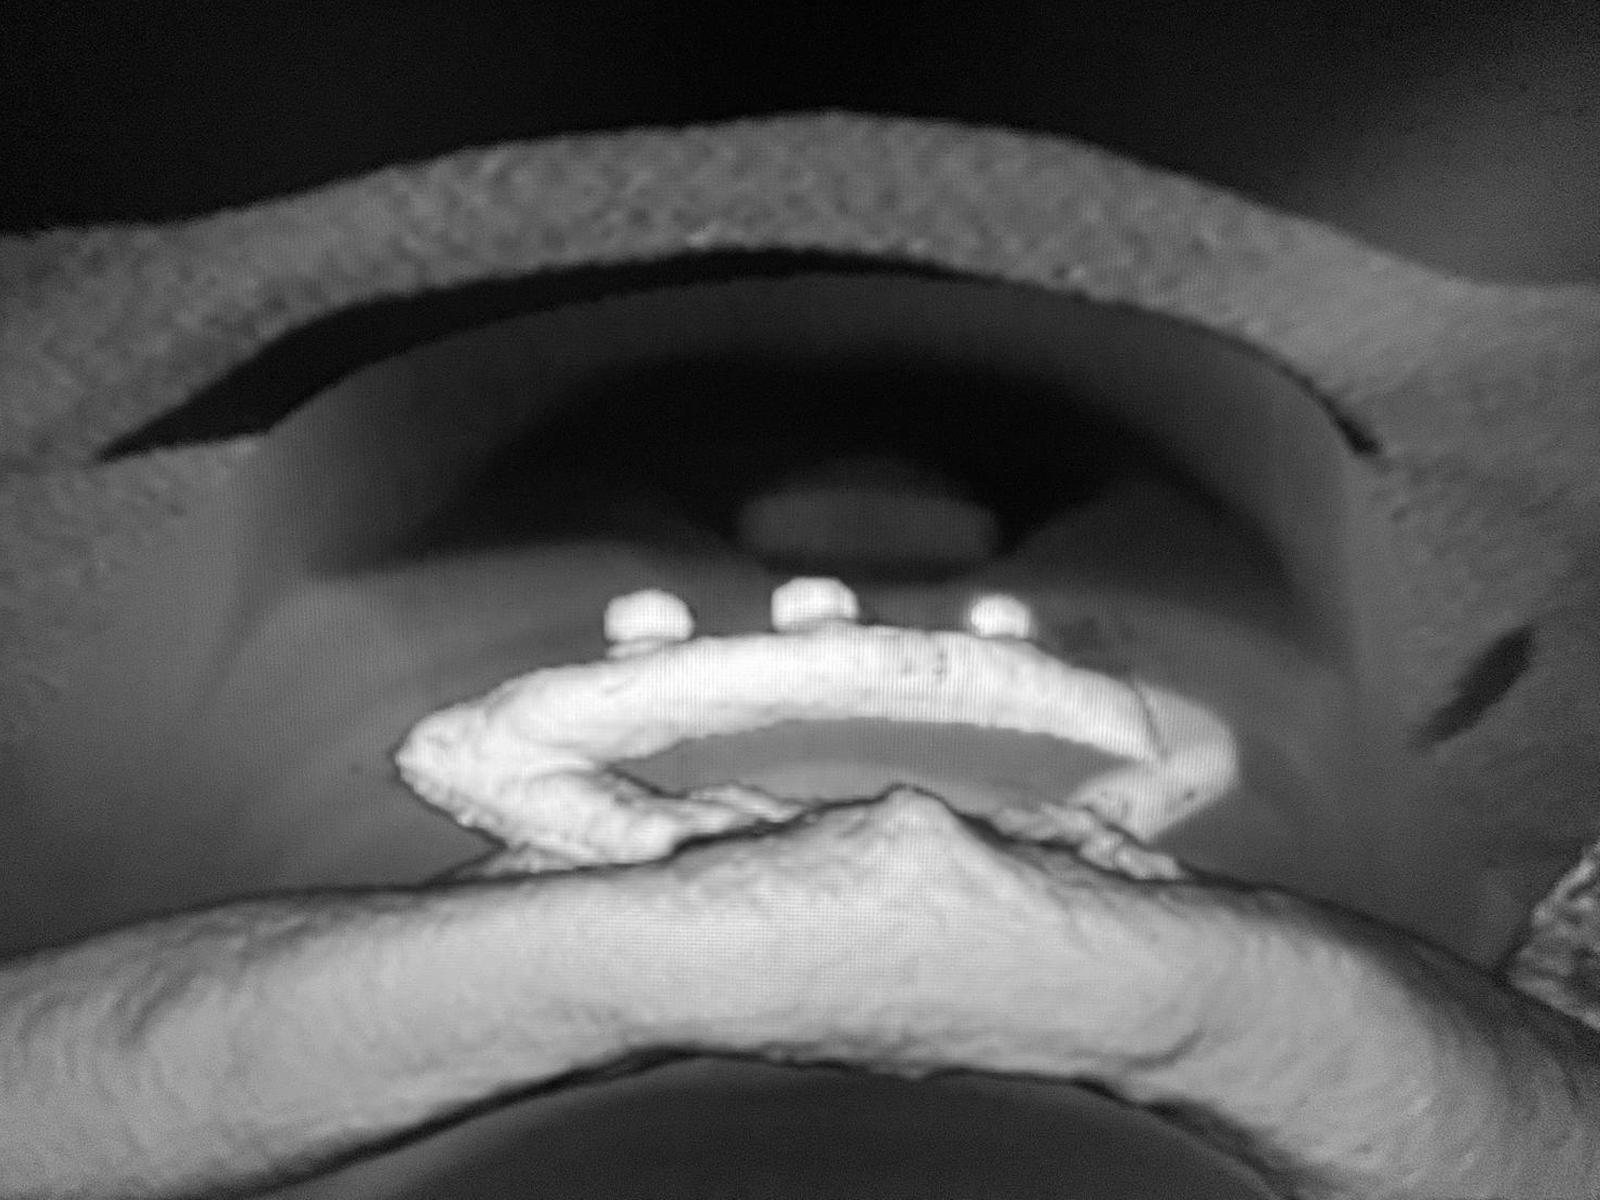

2. KONCEPT 2 in V / inovatívna implantačná metodika Dr. Drábika

Naša unikátna implantačná metodika, vyvinutá priamo u nás, bola prvý krát úspešne realizovaná už v roku 2022 na klinike ESTHE. Predstavuje nádej pre pacientov, ktorí doteraz nemali možnosť získať stabilnú zubnú náhradu pre nedostatok kosti.

Unikátny princíp zákroku.

Princíp spočíva v implantovaní dvoch monoimplantátov v extrémnom uhle. Tieto implantáty sú následne priamo v ústach pacienta prepojené titánovým strmeňom pomocou špeciálnej intraorálnej zváračky. Na strmeni sú umiestnené špeciálne atačmenty (úchyty), ktoré slúžia na pevnú fixáciu hybridnej protézy.